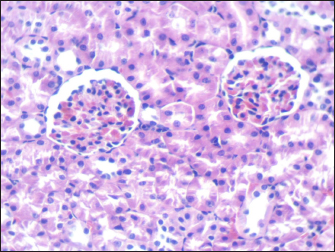

Mouse liver from the control group shows a normal radiant arrangement of the hepatic cells (Fig. 1). Pathological changes in treated liver sections showed an increase in the immune cells’ infiltration, and marked congestion were observed in almost all mice. In group 1, there was hemorrhage, congestion, and degenerated cells (Fig. 2). In group 2, there was congestion of the central vein, infiltration of immune cells, and degeneration of hepatocytes (Fig. 3). Whereas in group 3, the previously mentioned changes were markedly intensified with severe hemorrhage and marked sinusoidal dilatation (Fig. 4). Mouse kidney of control group shows normal cellular appearance (Fig. 5); however, pathological changes in treated kidneys sections reveals congestion, tubular necrosis and cast in some tubule’s lumen, group 1 (Fig. 6). In group 2, there was congestion, tubular necrosis, necrotic debrites in the tubuli lumen and cast (Fig. 7). Whereas in group 3 there was marked congestion, tubular and cellular necrosis, necrotic debrites in the tubular lumen and degenerated cells (Fig. 8).

Fig. 5. Section of mouse kidney of control group shows normal cellular appearance (H and E, ×400).

Histopathologically, the livers and kidneys from the BDL group exhibited significant morpho-structural alterations Figures 18. Lorazepam-treated mice showed severe congestion, hemorrhage, and hepatocellular degeneration in liver sections with greater severity such as in a dose-limited manner. Such histological changes resemble those reported by Chatila (2000) who also described similar findings in drug-induced liver diseases. Infiltration of immune cells and sinusoidal dilatation are observed, indicating an inflammatory response which is consistent with this idea as independent findings by Dong et al. (2020) correlated these with severe liver injury.

Pronounced congestion, tubular necrosis, and intraluminal casts were found in the kidneys. It has been reported that tubular necrosis and obstruction play a critical role in the pathophysiology of AKI (Basile et al., 2012; Kanagasundaram, 2015), which is consistent with markers for acute kidney injury. Histopathology score is dose dependent confirming the relation of the higher dose to more extent of organ damage suggesting toxicity in the form of toxic dose reaction, has been detected in lorazepam.